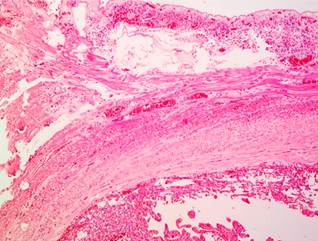

Pathology examination reported a well-circumscribed benign mesenchymal tumor located in the submucosa and muscularis propria, consisting of thin-walled vascular channels without atypia or mitosis, filled with abundant blood, consistent with an ulcerated capillary hemangioma (Figures 3 and 4). The patient showed a favorable clinical course, with no new bleeding episodes, improved hemoglobin levels, and good tolerance to oral intake, allowing for discharge. She remains asymptomatic in outpatient follow-up.